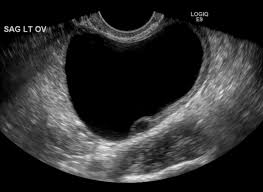

Simple cysts that are smaller than 4.2 cm disappear with little medication. If the follicle containing the ovum doesn't rupture during ovulation, a follicle cyst of more than 2.5cm diameter may result. Report was given to my dr who called me with the results. I am concerned because i have been having vaginal bleeding and pain and it is larger than any other ovarian cyst i have ever had before. The largest type of ovarian cyst is called a cystadenoma. However, some may reach sizes of 8 to. Ovulation happens when these cysts are around 2 to 3 cm in size. Ovarian cysts can cause an increase to ca125 levels.

Around ovulation, the follicle measures around 2 cm, so this is a little bigger. Report was given to my dr who called me with the results. As far as cysts go, it is not that large and still on the small side. In general, ovarian cysts can range from under 0.5 inches (1.27 cm) to more than 12 inches (30.48 cm). In a small minority of cases, cysts can be cancerous. If you're having abdominal pain or discomfort that doesn't seem quite normal, it's possible that you have an ovarian cyst. Ovarian cysts in the neonate are exceedingly rare. I am due to have an operation, well actually i was supposed to have it last monday but it got cancelled after waiting 7 hours and im still awaiting a date.

It is estimated that 5% of all abdominal masses in the first month of life are ovarian cysts. I had gone into an urgent care clinic due to the excruciating pain radiating from my abdomen to my legs and lower back. They said they couldn't even see my ovaries on the ultrasound. The biggest neoplastic cyst in recorded history was 328 pounds. The largest type of ovarian cyst is called a cystadenoma. Hi all, after a year of intensely painful periods and recent horrendous pelvic pain, as well as a very late period, i've found out this week i have a 13 x 13cm cyst on my left ovary, with lots of other cysts all over. I was diagnosed as having a 9.1 cm ovarian cyst in my right ovary two days ago. Ovarian cysts are common among women of all ages. In general, ovarian cysts can range from under 0.5 inches (1.27 cm) to more than 12 inches (30.48 cm). He said according to the report, there no urgency, meaning. However, some may reach sizes of 8 to. 2cm is just a little bit more than 3/4 of an inch. This form of ovarian cyst usually doesn't cause any symptoms and goes away on its own.